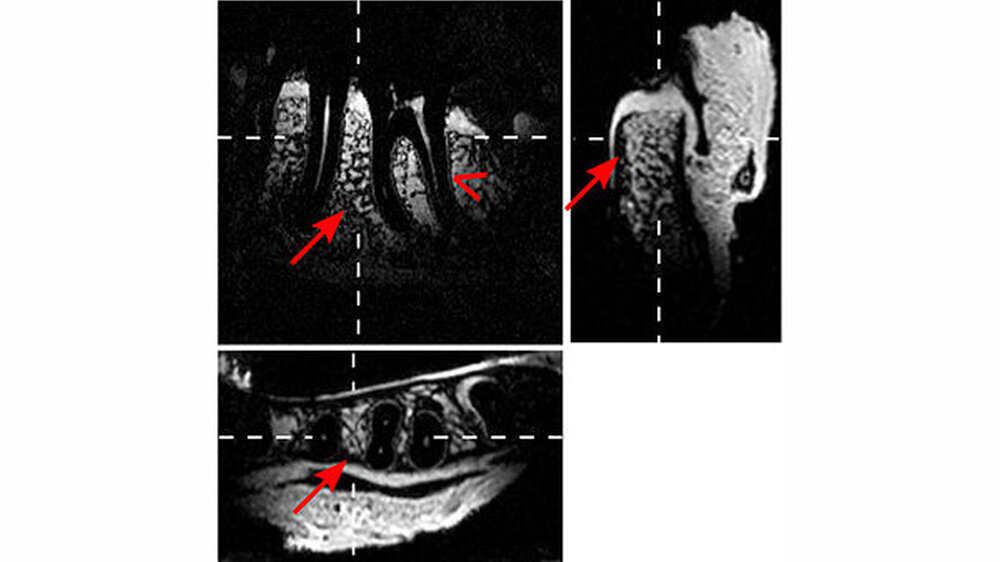

Kieferknochen, Gefäß-Nerven-Stränge und das Weichgewebe werden dargestellt

„Die neue Methode trägt wesentlich dazu bei, dass die Magnetresonanztomografie in Zukunft die konventionelle Röntgendiagnostik in der Zahn-, Mund- und Kieferheilkunde ersetzen wird“, sagt Oberärztin Prof. Katja Nelson. „Vor einer Operation können wir Kieferknochen, Gefäß-Nerven-Stränge und das umgebende Weichgewebe darstellen und so bei der Operation besonders schonend vorgehen, ohne den Nerv zu treffen.“ Da für die Patienten keine Strahlenbelastung besteht, könnten Ärzte die Bildgebung auch erstmals zur regelmäßigen Kontrolle des Heilungsverlaufs einsetzen.

Kernstück der Dental-MRT-Methode ist eine etwa einen Zentimeter hohe Spule aus zwei parallel angeordneten Metallringen. Aufgrund ihrer elektrophysikalischen Eigenschaften verstärkt die Doppelspule die MRT-Signale des umschlossenen Gewebes. Dadurch wird eine Auflösungsgenauigkeit von etwa einem Drittel Millimeter erreicht, die der des Röntgens nahekommt. Die Spule funktioniert ohne Energie und ist für den Patienten absolut ungefährlich. „Unsere Lösung für ein altes Problem der Zahnheilkunde ist an sich technisch recht einfach und trotzdem eine echte Innovation“, sagt Studienleiter Jan-Bernd Hövener.

Mithilfe der entwickelten drahtlosen, intraoralen, induktiv-gekoppelten Spulen kann demnach ein MRT in einer ausgewählten Region mit hoher Auflösung in einer klinisch möglichen Zeit von etwa vier Minuten erstellt werden. In der Vergangenheit wurde den Forschern zufolge schon versucht, das MRT-Signal mit Einzelspulen zu verstärken, allerdings ohne durchschlagenden Erfolg. Die jetzt verwendete Doppelspule erlaube nun Bilder von wesentlich höherer Qualität. Dass die Spule kein Kabel benötigt, erleichtere zudem den Einsatz für den Patienten. Die Freiburger Forscher haben die neue Methode bereits patentieren lassen.